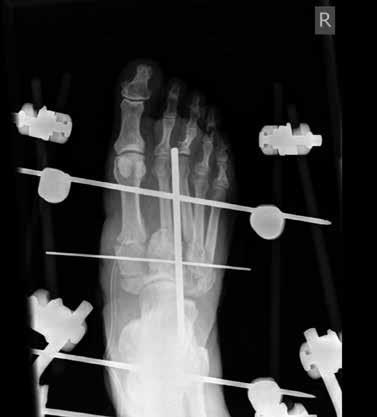

Die Art und Weise einer adäquaten operativen Therapie wird stark kontrovers diskutiert. Nach Auffassung der Verfasser ist die externe Fixation ein geeignetes, effektives und äußerst variables Verfahren mit relativ geringer Komplikationsrate. Es können sowohl aktive als auch inaktive Osteoarthropathien mit einem Fixateur externe behandelt werden. In der Regel wird eine Arthrodese oder zumindest eine straffe und belastbare Pseudarthrose hergestellt, die eine schmerzfreie Mobilisation unter Vollbelastung ermöglicht.

Das Versorgungskonzept bei der operativen Schiene ähnelt dem konservativen Konzept. Die Fixateur-externe-Therapie wird für 6 bis 12 Wochen durchgeführt. Die Verfasser ziehen 8 bis 12 Wochen vor, die Therapiedauer ist aber abhängig von der Compliance und der Mitarbeit des Patienten und kann sich auf ein Minimum von 6 Wochen reduzieren. Anschließend hat sich eine Versorgung in einer Unterschenkelorthese für weitere 3 bis 9 (12) Monate bewährt. Ist es zu einer knöchernen Konsolidierung bzw. straffen Pseudarthrose gekommen, kann der Patient mit orthopädischen Maßschuhen versorgt und mobilisiert werden.

Der operative Zugang erfolgt abhängig von der Lokalisation der Charcot-Arthropathie. Bei ausgeprägten Deformitäten ziehen die Verfasser einen bilateralen Zugang vor. Neben einer sorgfältigen Entfernung avitalen Knochengewebes erfolgt gegebenenfalls eine Resektion infizierten Gewebes sowie eine Abtragung von Pseudoexostosen. Die alleinige Abtragung von Pseudoexostosen kann in einigen Fällen als alleinige operative Behandlungsmethode ausreichend sein. Bei vorhandenen Ulzera bzw. Infektionen werden gentamicinhaltige Antibiotikaträger appliziert. Autologe Spongiosa bzw. Knochenersatzstoffe können in die restlichen Defekte nach Reposition und Anfrischung der Gelenkpartner interponiert werden. Fixateur-Pins mit zentralem Gwinde werden in die Metatarsaliaköpfchenreihe, den Calcaneus und die Tibia eingebracht. Nach Reposition des Fußes wird der Fixateur externe montiert, in der Klinik der Verfasser der Hoffmann-II-Fixateur als bilaterale Rahmenkonstruktion (Abb. 4). Zielvorgabe für die dreidimensionale Stellungskorrektur ist hierbei die lotgerechte Einstellung des Fußes in der frontalen Ebene mit plantigrader Belastbarkeit (Abb. 5a u. b). Während der Tragedauer des Fixateurs erfolgt eine vollständige Entlastung der betroffenen Extremität. Der Patient ist für diese Zeit im Rollstuhl oder bestenfalls an Unterarmgehstützen mobilisiert. Sechs bis zwölf Wochen postoperativ wird das Material entfernt. Die vollständige Materialentfernung kann ohne Narkose unter Analgesie durchgeführt werden. Bis zur Versorgung mit einer Orthese wird der Fuß vor der Überbelastung des reponierten Fußes mit einem Cast geschützt.